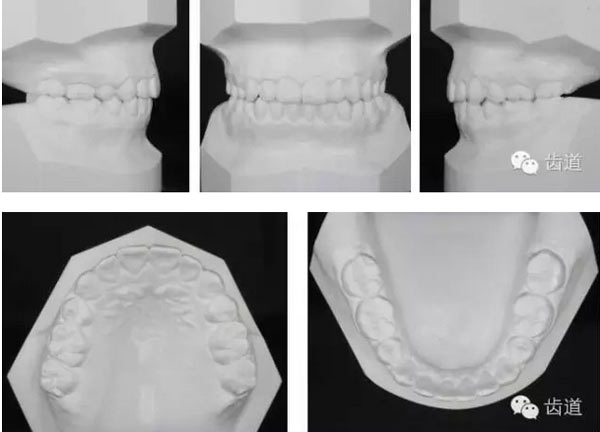

治療后模型

牙與牙弓:25腭側(cè)完全錯(cuò)位導(dǎo)致26前移,上牙列重度擁擠,下牙列中度擁擠,上牙弓尖圓形,下牙弓卵圓形,第三磨牙牙胚存,18與28牙冠較小且形態(tài)不良

橫向:上下牙弓寬度不匹配,下牙弓寬度較上牙弓大,左側(cè)自第一磨牙開(kāi)始至側(cè)切牙均為反合。上牙列中線左偏,下牙列中線右偏。

矢狀向:安氏II類,骨性II類,下頜后縮,上前牙唇傾

垂直向:高角,垂直生長(zhǎng)型,前牙開(kāi)合

橫向不調(diào):牙弓寬度輕度不調(diào)的解決在于上頜適當(dāng)?shù)臄U(kuò)弓與后退左上牙列,以及下頜適當(dāng)?shù)目s弓與下磨牙前移,矯治后上頜磨牙寬度由41.8mm變?yōu)?3.1mm,下頜磨牙寬度由39.6mm變?yōu)?7.8mm。